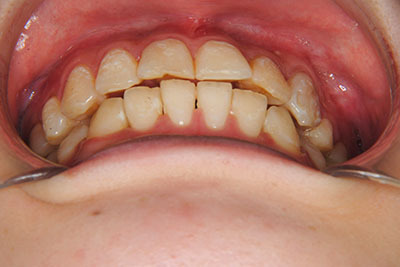

⑧リスクと副作用:マルチブラケット装置(T21ブラケット)を初めてつけてから3,4日、食事の時に歯が少し痛かったとのことでした。治療後のエックス線写真で、歯根吸収はほとんど観察されませんでしたが、歯肉を診ると残念ながら下の真ん中の前歯2本の間に若干の歯肉退縮(ブラックトライアングル)が生じていました。

マルチブラケット装置(T21ブラケット)に加えて口の中のゴムをたいへん頑張って使っていただいた結果、治療前の予想期間1年から1年半であったところ、10カ月で動的治療を終了できました。上下真ん中のズレも治りぴったりになりました。 これからは歯並びの維持安定のためリテーナー(保定装置)を使いながら定期健診となります。